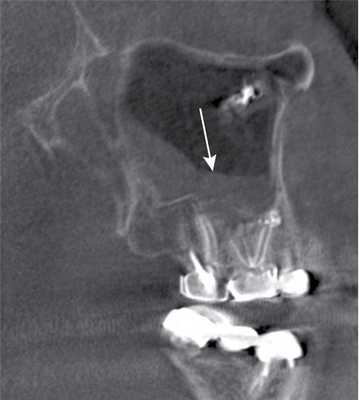

Больная Б., 43 года, проходила исследование в отделении компьютерной томографии КОКБ по поводу объемного образования среднего уха. В качестве случайной находки выявлена правосторонняя одонтогенная киста (рис. 6, а, б; 7).

Рис. 6. Магнитно-резонансная томограмма верхнечелюстных пазух, изображения в режимах Т1 (а) и Т2 (б), аксиальная проекция.

Рис. 7. Контрольная рентгеновская компьютерная томограмма в аксиальной проекции, мягкотканный режим.